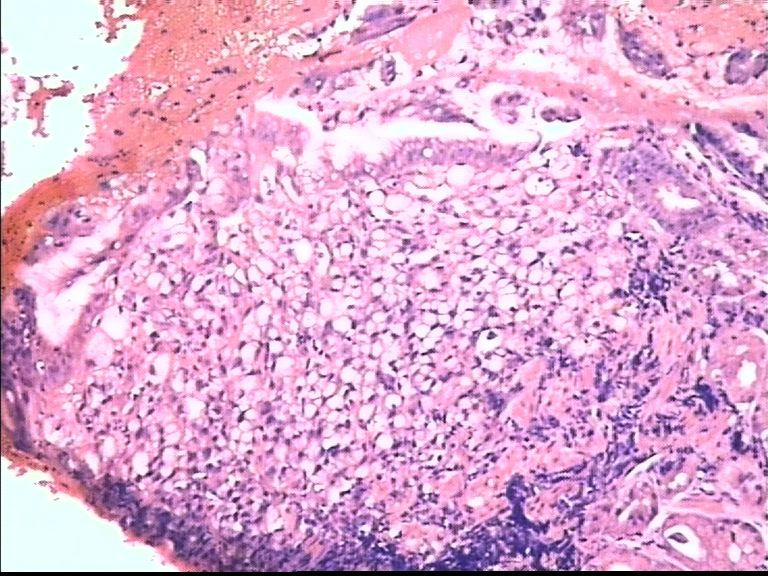

胃部溃疡3cm 53岁 男

仅此局部形态,应该是印戒细胞癌,最好有更多的背景资料

印戒细胞癌

倾向印戒细胞癌

诊断印戒细胞癌

印戒细胞癌高度可疑,建议做:CK、CD68、PAS帮助诊断。